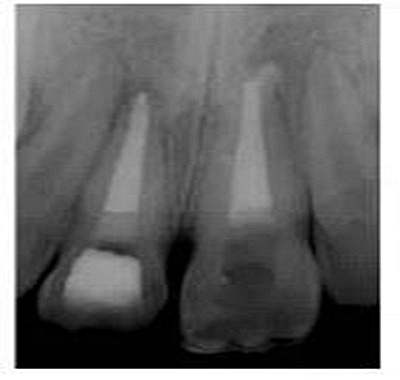

切端則采用透明樹脂,最后使用釉質(zhì)樹脂(Amaris, VOCO, Cuxhaven, Germany)。21的樹脂修復采用類似的方式。修復初步成型,拋光,恢復干燥牙釉質(zhì)的顏色。攝片顯示樁在根管內(nèi)位置合適(圖15)。最后一次復診精修、拋光充填體,完成治療。